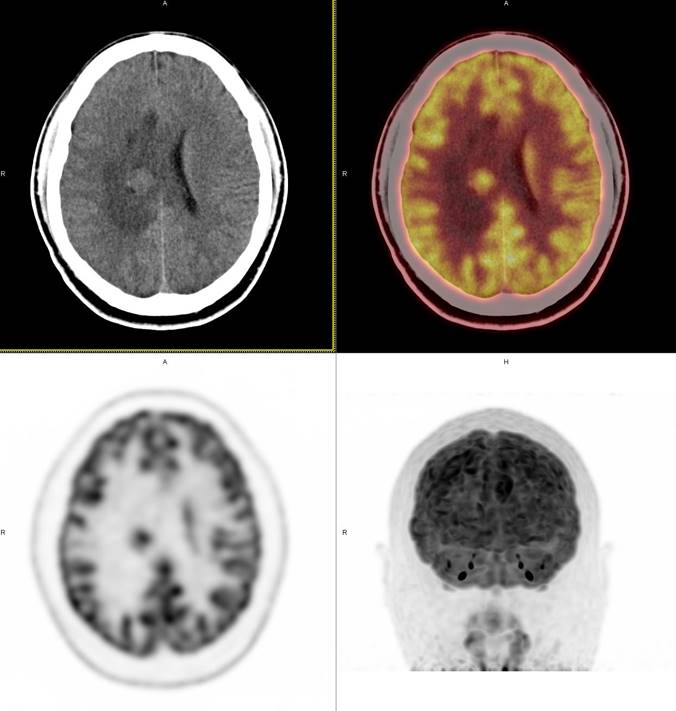

PET/CT影像圖

圖1

圖2

圖3

圖4

PET/CT檢查

影像診斷: 右側(cè)側(cè)腦室旁腦實(shí)質(zhì)內(nèi)結(jié)節(jié),代謝異常增高(SUVmax 12.13),伴瘤周水腫。

病理診斷:腦膜瘤二級(jí)

此例,PET/CT全身檢查不僅排除了轉(zhuǎn)移瘤的可能性,增高的SUV值無(wú)創(chuàng)地鑒別腦膜瘤的良惡性,充分體檢PET/CT大視野、形態(tài)與功能影像結(jié)合的優(yōu)勢(shì)。